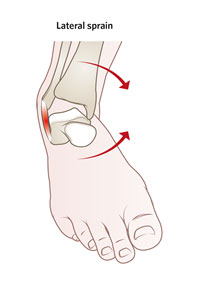

足踝扭傷,俗稱「拗柴」,是最常見的足踝關節疾病之一。足踝扭傷(拗柴)是因為內翻或外翻扭傷而導致韌帶撕裂,通常會伴隨疼痛、腫脹甚至行走困難。

常見的足踝扭傷(拗柴)情況,例如在不平坦的路面上行走或跑步、走路時踩空或者穿著不合適的鞋子(例如: 高跟鞋),都很容易導致踝關節內翻或外翻扭傷,通常是內翻扭傷(±95% ),外翻扭傷較少 (±5%)。

| 足踝內翻扭傷 |

外側翻踝腫痛 |